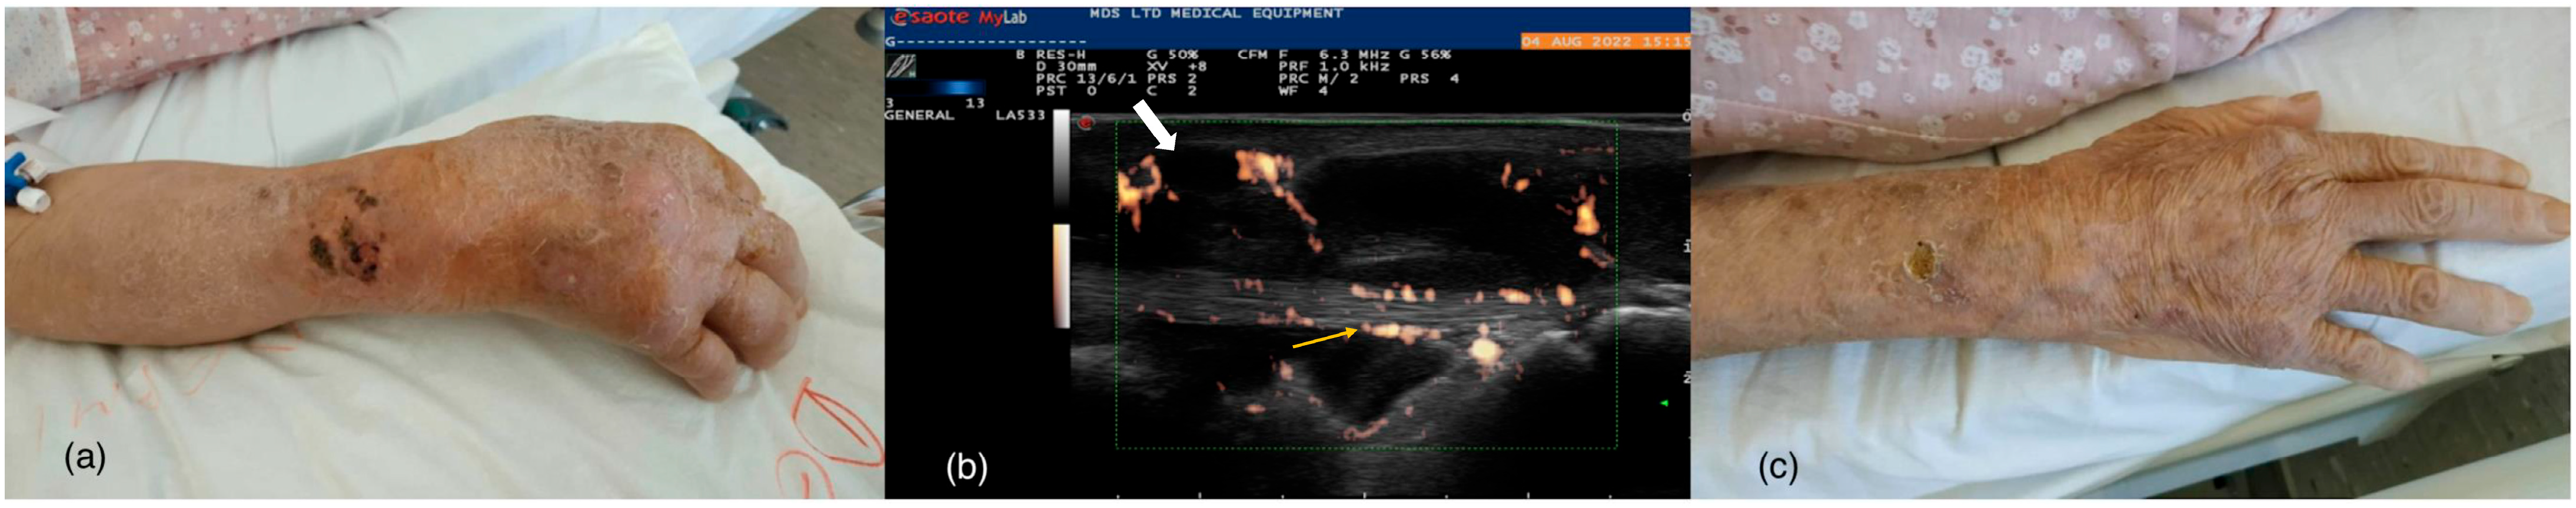

| Present case | 81/F | RA, atrial fibrillation, mitral valve regurgitation, arterial hypertension, dyslipidemia, and osteoporosis | MPz 6 mg/d | Scedosporium apiospermum | Skin | IV VCZ 400 mg/d; Switch to PO VCZ 200 mg/d (due to VCZ-induced liver dysfunction) for 1 month | Reccurence; ITZ 200 mg/d |